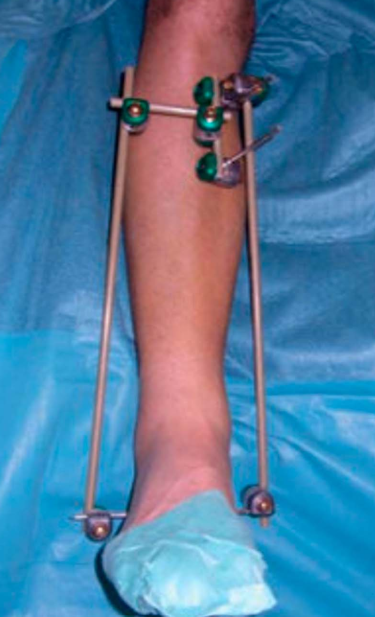

在既往的临床实践中,一期外固定架固定,待软组织情况改善后的二期确切内固定治疗,被证实是合并软组织损伤的Pilon骨折的有效方法。

Pilon骨折的手术治疗目的,是恢复胫骨远端关节面的平整,恢复下肢力线以及胫距关节面的良好匹配,在术前CT扫描的准确评估下,采用合适的手术入路治疗。